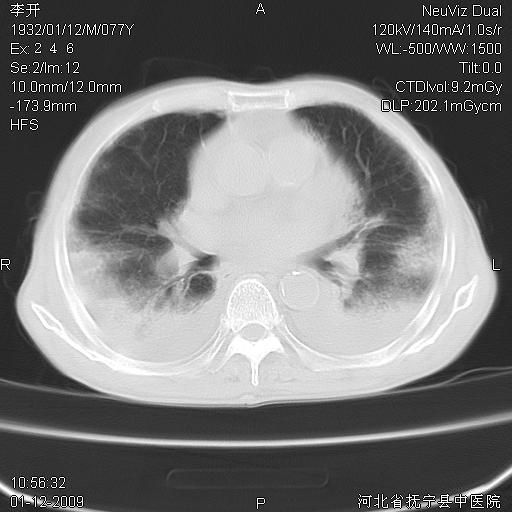

以下是引用黑白光影在2009-1-19 16:49:00的发言:[br]心衰肺水肿;心包、胸腔积液;冠脉钙化;肺部感染。